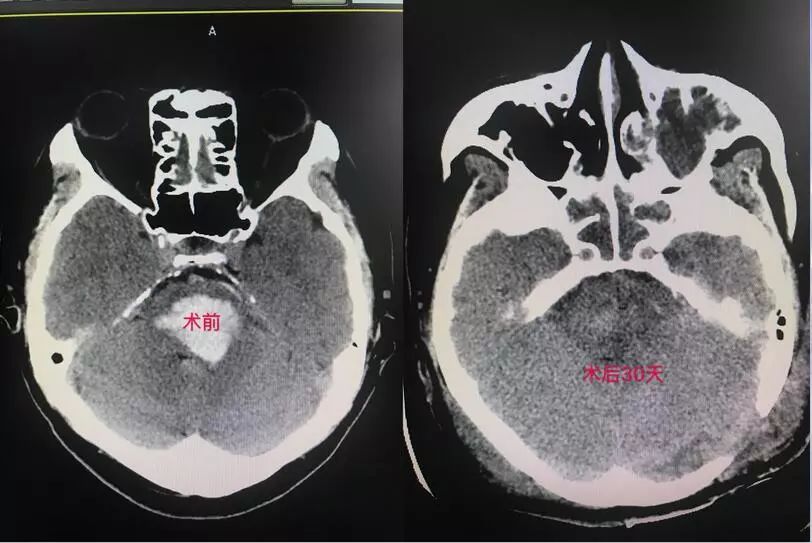

4、脑干出血的手术:

二、脑血管造影、颅内动脉支架、动脉瘤夹闭、栓塞,血管搭桥治疗烟雾病等缺血性脑血管病。脑出血及脑干出血的精准微创手术治疗。